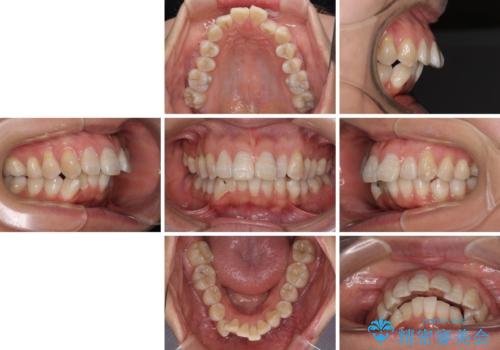

- 上顎歯列の出っ歯を気にして来院された患者様です。

骨格的に上顎歯列が前方位にあり、口元の突出感が顕著な状態で、上下左右の第一小臼歯4本を抜歯して、ワイヤー装置での抜歯矯正を行うこととしました。

ご本人がびっくりするくらい劇的に口元の突出感が改善され、大変満足のいく仕上がりとなりました。